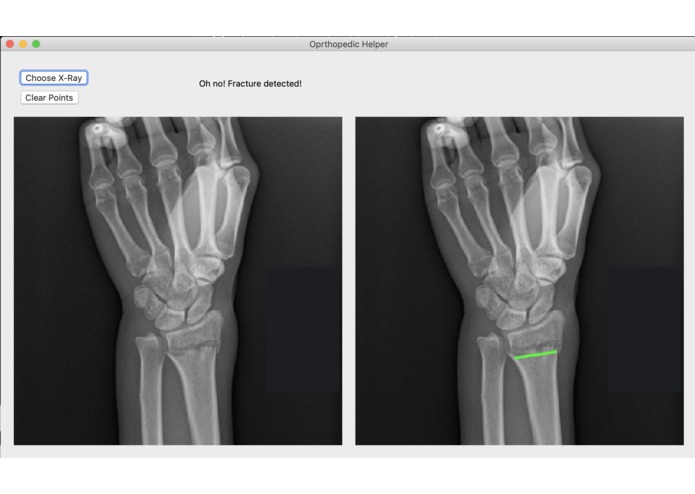

Broke Detector is a simple tool to help analyze the site of wrist injury. It helps doctors decide a) whether the bones are broken or not (which is admittedly very simple for humans, but not for computers) and b) provides tools such as a protractor to provide an objective measurement of how misaligned bones are. Broke Detector aims not to replace the orthopedist, but to aid them.

The actual detection algorithm is the guts of this project (no machine learning involved). The process is as follows: Thresholding: Reasons for this will be listed in the next section, we did this using color histograms to determine the percentile of certain pixel values. Edge detection: We used a simple Söbel kernel (however, not the default opencv one) to handle edge detection, as it was simple to detect only horizontal edges. Hough transform: This is the guts of the algorithm, which decides where horizontal lines are in the X-Ray. It sounds dumb, but choosing the lowest isolated horizontal line almost always results in finding the break in the bone. Flask: We developed a locally hosted web application which supports uploading from the computer. The HTML formatted site displays the results of the Python calculations.

The desktop interface was written in Python as well, using the wxPython framework for the GUI.